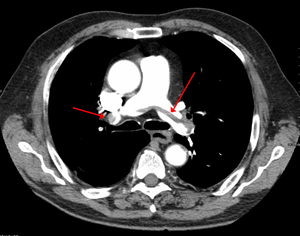

| Chest spiral CT scan with radiocontrast agent showing multiple filling defects both at the bifurcation ("saddle" pulmonary embolism) and in the pulmonary arteries. | |

CT pulmonary angiography (CTPA) is a pulmonary angiogram obtained using computed tomography (CT) with radiocontrast rather than right heart catheterization. Its advantages are clinical equivalence, its non-invasive nature, its greater availability to people, and the possibility of identifying other lung disorders from the differential diagnosis in case there is no pulmonary embolism. Assessing the accuracy of CT pulmonary angiography is hindered by the rapid changes in the number of rows of detectors available in multidetector CT (MDCT) machines.[45] According to a cohort study, single-slice spiral CT may help diagnose detection among people with suspected pulmonary embolism.[46] In this study, the sensitivity was 69% and specificity was 84%. In this study which had a prevalence of detection was 32%, the positive predictive value of 67.0% and negative predictive value of 85.2% (click here to adjust these results for people at higher or lower risk of detection). However, this study's results may be biased due to possible incorporation bias, since the CT scan was the final diagnostic tool in people with pulmonary embolism. The authors noted that a negative single slice CT scan is insufficient to rule out pulmonary embolism on its own. A separate study with a mixture of 4 slice and 16 slice scanners reported a sensitivity of 83% and a specificity of 96%, which means that it is a good test for ruling out a pulmonary embolism if it is not seen on imaging and that it is very good at confirming a pulmonary embolism is present if it is seen. This study noted that additional testing is necessary when the clinical probability is inconsistent with the imaging results.[47] CTPA is non-inferior to VQ scanning, and identifies more emboli (without necessarily improving the outcome) compared to VQ scanning.[48]